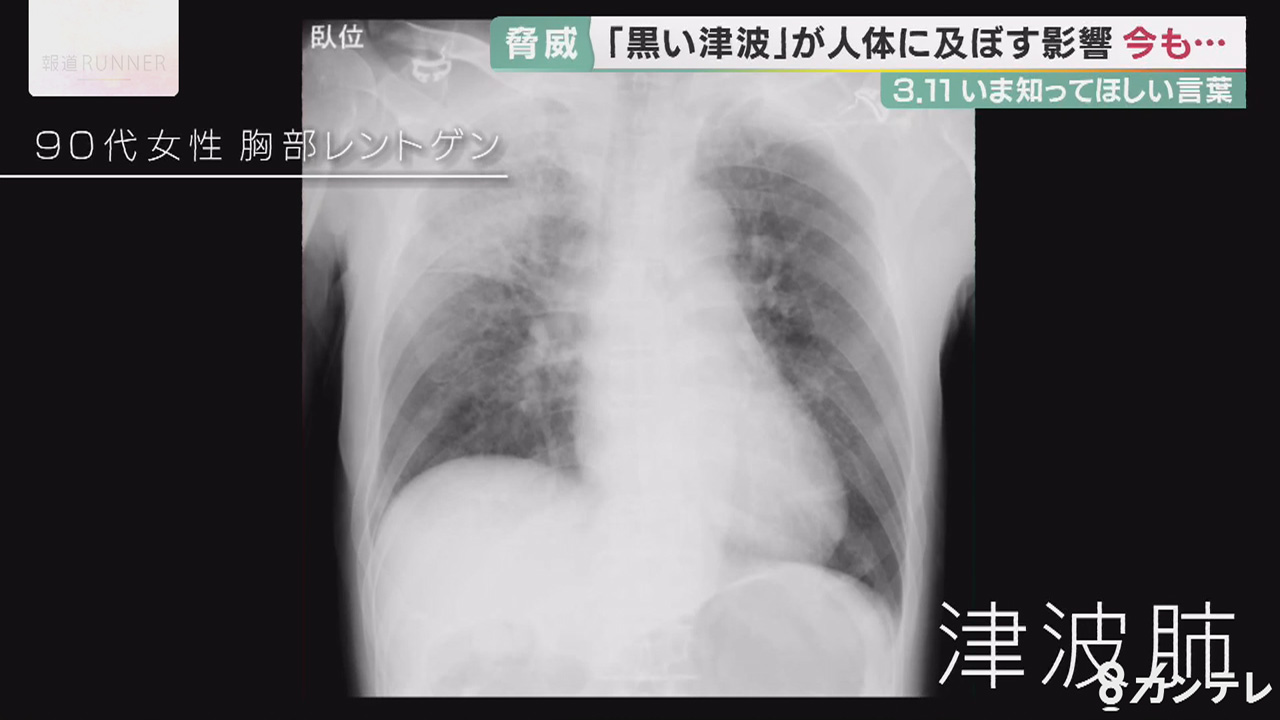

「黒い津波」に流された90代の女性のレントゲン写真。広範囲に白い影があり、「津波肺」と呼ばれる重い肺炎症状がみられます。海水とともに汚れた泥などを飲み込んだことが原因とみられ、女性は搬送から4日後に死亡しました。